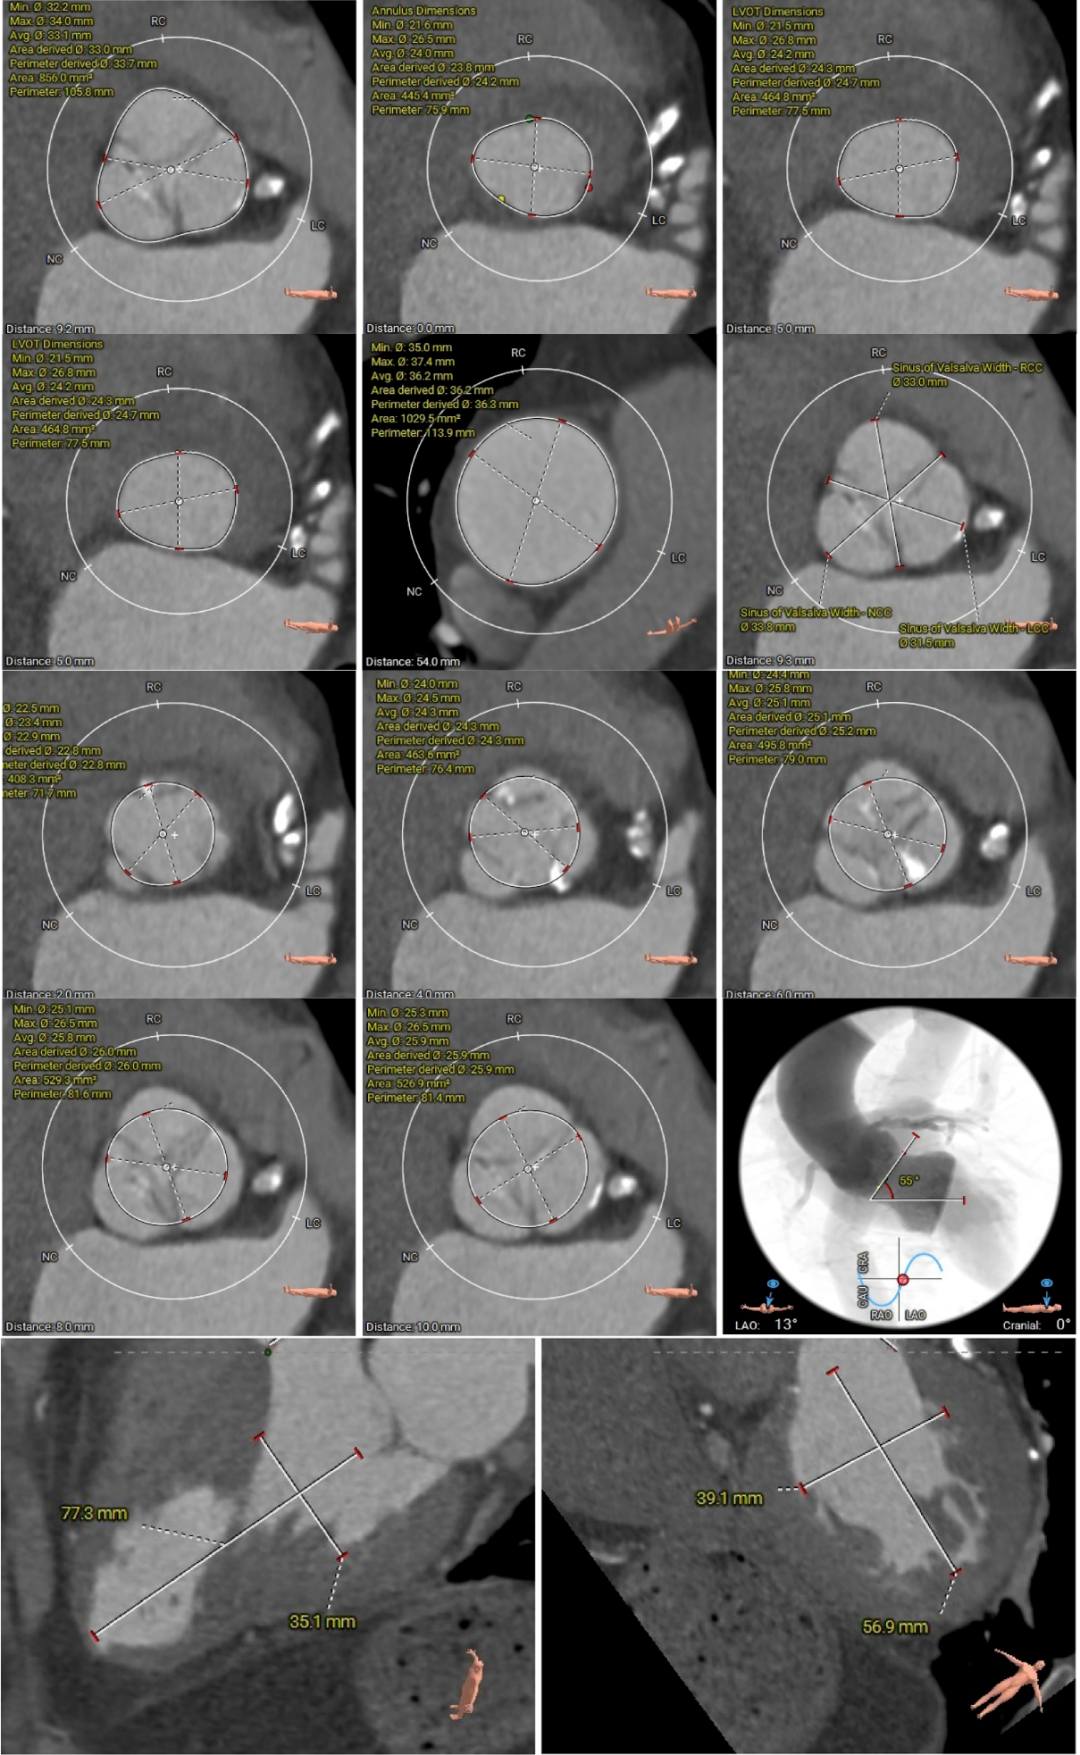

进一步评估显示,患者瓣膜狭窄程度重,瓣叶钙化明显,左心室腔径偏小,手术中对器械通过、瓣膜释放以及循环稳定性的要求都更高。团队结合术前影像和整体身体状况,制定了周密的介入治疗方案,并做好相关风险预案。

CT评估

瓣膜评估

近日,昆山市中医医院心内科团队又成功为一名82岁高龄患者实施经导管主动脉瓣置换术。该患者主动脉瓣口面积仅0.2cm²,而正常成人主动脉瓣口面积一般约为3至4cm²。与此同时,患者还合并重度钙化的二叶式主动脉瓣、轻中度反流,左心室腔径偏小,并有帕金森病病史。多重高危因素叠加,意味着术中导丝跨瓣难度大,循环波动耐受差,整体风险很高。

术前评估越细,术中把握才越稳